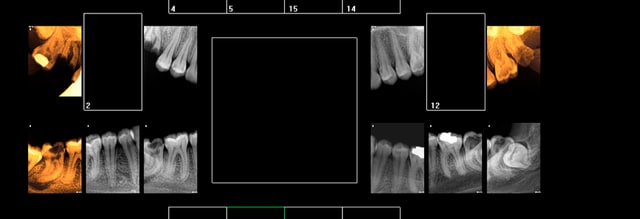

Patiente CMU. 20 ans venue en urgence pour douleurs sur 37 ( tu m'étonnes ). M'a séché 2 rendez vous d'une heure depuis. Le premier "malade", et le 2 eme foutage de gueule (appelée la veille pour confirmer).

Vu la quantité d'extractions à faire 37 47 38 48 16 18 28 plus éventuellement d'autres, j'aurais adressé la patiente à un stomato pour intervention sous AG en une fois.